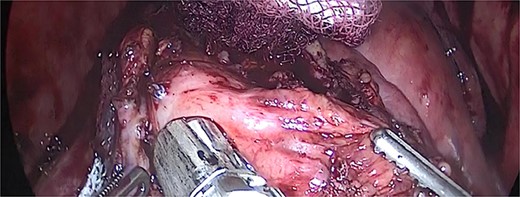

We performed adhesiolysis, used a harmonic scalpel to release intestinal loops and identified the gastric pouch (which was tight and measured < 15 cm long), remaining stomach, gastrojejunostomy and the common limb (∼200 cm), the total intestinal length was 600 cm (Fig. 2). We proceeded to make a new gastric pouch with a black staple (60 mm) and performed a gastro-gastro anastomosis with a purple staple (45 mm) (Fig. 3). The angle of Treitz was identified, and we found the jejunojejunostomy at 200 cm (Fig. 4). We later identified the gastroileal anastomosis, proceeded to resect that segment of 15 cm (Fig. 5) and the surgical procedure was completed.